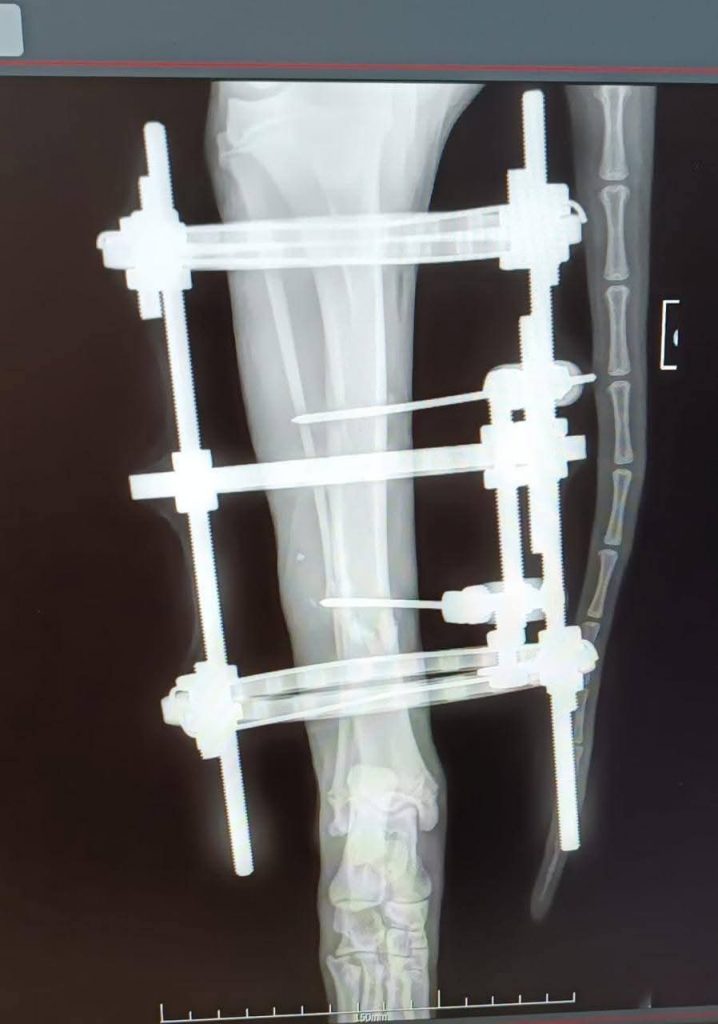

Orso ist in Italien verunfallt, dabei wurden seine beiden Hinterläufe zertrümmert. Er wurde in einer Klinik wieder zusammengesetzt und braucht jetzt in Deutschland eine Pflegestelle – uns! 🙂